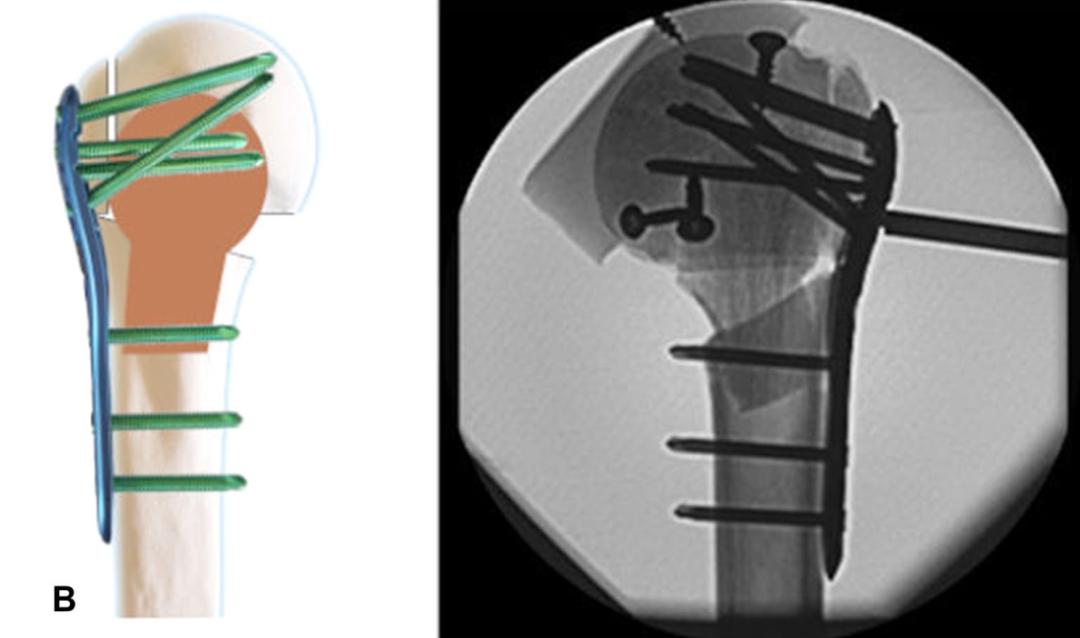

笔者团队在2010年首次提出肱骨近端解剖髓内支撑概念[8,12],并以此概念使用修整后的解剖型异体腓骨(图1)进行临床试验,腓骨支撑组随访33.5(24-48)个月,解剖腓骨支撑无头内翻与螺钉切割,总体肱骨头坏死率为10.6%,但因患者满足当前功能,均未行翻修手术,术后2年功能优良率达100%。通过形态学研究[13]分析并比较了老年和年轻患者的髓腔解剖退变模式,以更好地从解剖学上了解肱骨近端髓腔形态,完善解剖髓内支撑概念。通过有限元分析[14]对比解剖髓内支撑结构联合锁定钢板能够较锁定钢板获得更好的抗剪切与抗扭转力。为了摆脱同种异体骨资源限制,团队设计研发了髓内支撑钉与钢板系统(图2)[9],并应用于老年Neer3/4部分肱骨近端骨折,结果显示手术时间与术中出血量与单纯钢板治疗无差异,1年以上随访显示畸形愈合率11.1%远低于钢板组,Constant评分、DASH评分、患者主观优良率均高于钢板组。

图2 髓内支撑钉与钢板系统